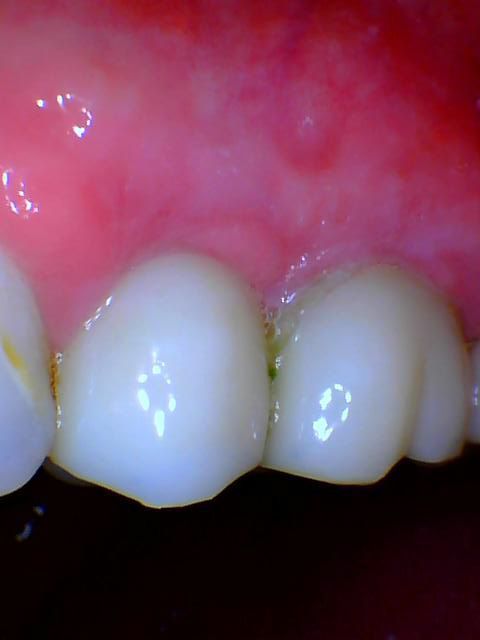

Dental implants provide both exceptional stability and functional benefits in addition to their attractive design. Dental implants function as natural teeth do because they stop jawbone loss and help maintain complete oral wellness. They serve multiple purposes because they replace single teeth, secure dentures, and restore complete sets according to individual requirements.

Dental implants represent a long-term investment that supports your oral health throughout your entire life. The implants enable better speech and comfortable chewing and restore confidence, which results in a quality of life similar to that of natural teeth. Dental implants become a permanent solution for dental issues when properly cared for because they can last throughout your lifetime. Parkway Restorative Dentistry offers patients the transformative benefits of dental implants.